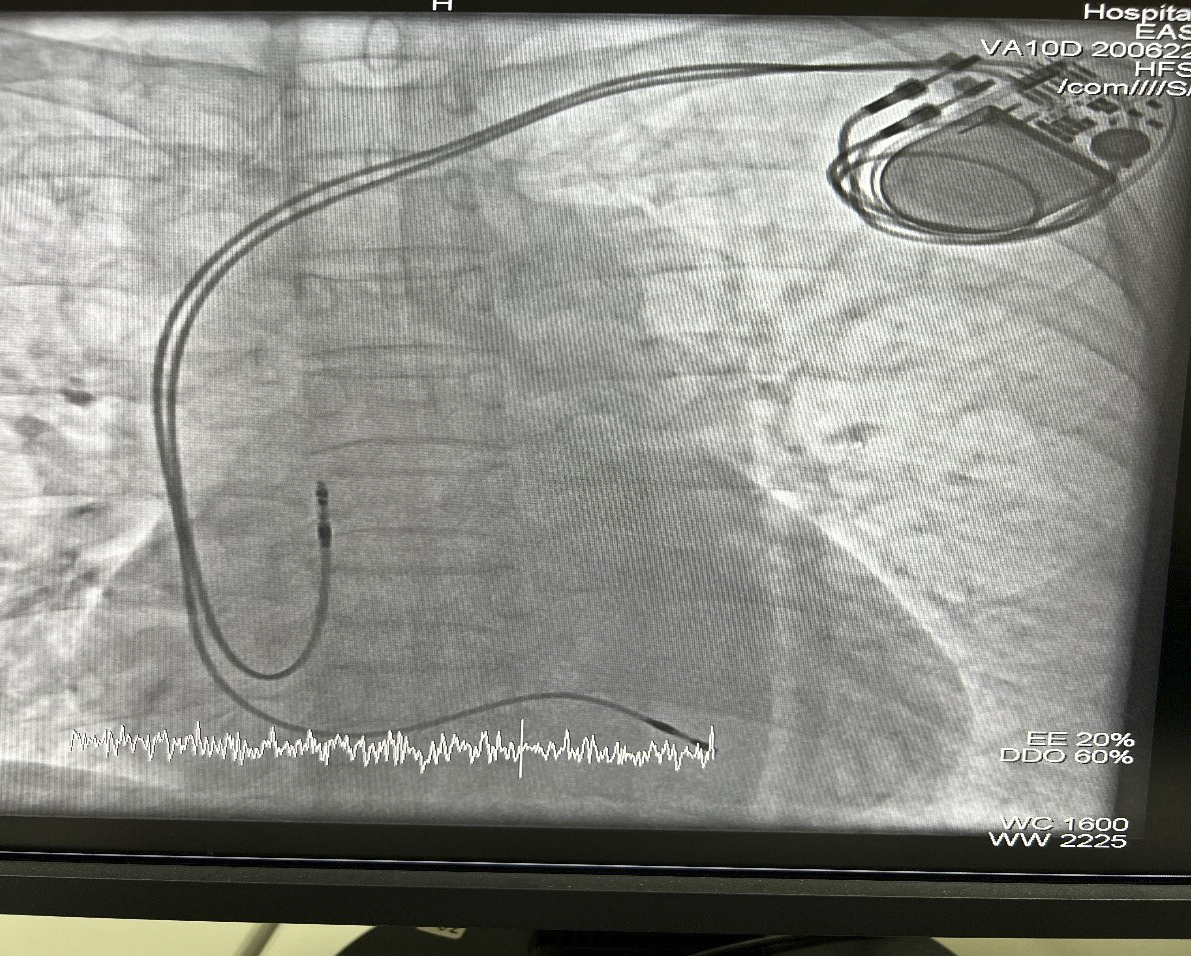

Hình 1: Máy tạo nhịp tim

Hình 2: Bệnh nhân sau cấy máy tạo nhịp tim